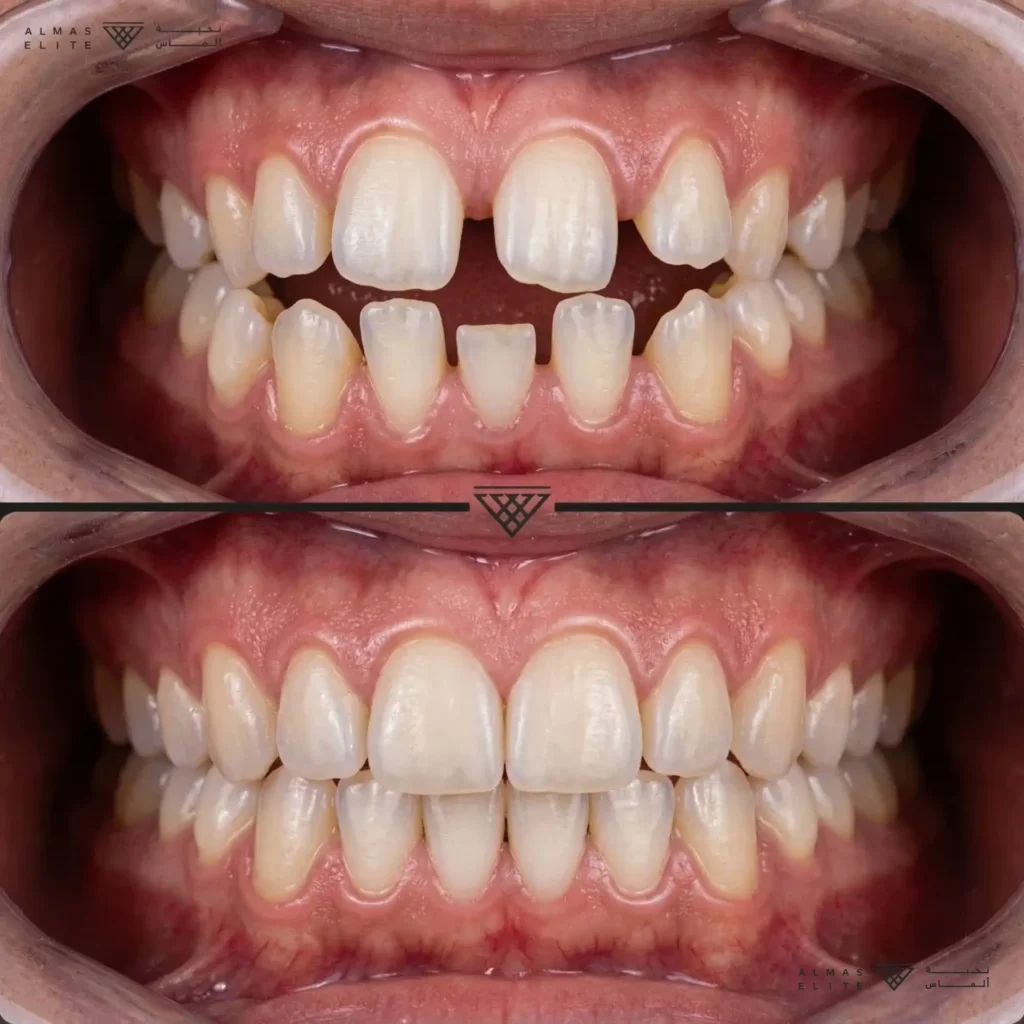

تقويم الأسنان في الرياض بإشراف استشاري بخبرة ممتدة منذ عام 2003

في نخبة ألماس الطبية، نقدم خدمات تقويم الأسنان الثابت والشفاف بإشراف

الاستشاري الدكتور فهد بن حمود القحطاني، خريج جامعة نيويورك (NYU)،

وصاحب خبرة ممتدة منذ عام 2003 في علاج حالات التقويم المختلفة في كل من القطاعين الحكومي والخاص داخل المملكة.

نعتمد على أحدث أنظمة وتقنيات تقويم الأسنان العالمية، مع خطط علاجية دقيقة ومخصصة لكل حالة،

تشمل المتابعة المستمرة والتوجيه العلاجي للمريض، لضمان نتائج مستقرة وابتسامة متناسقة على المدى الطويل.